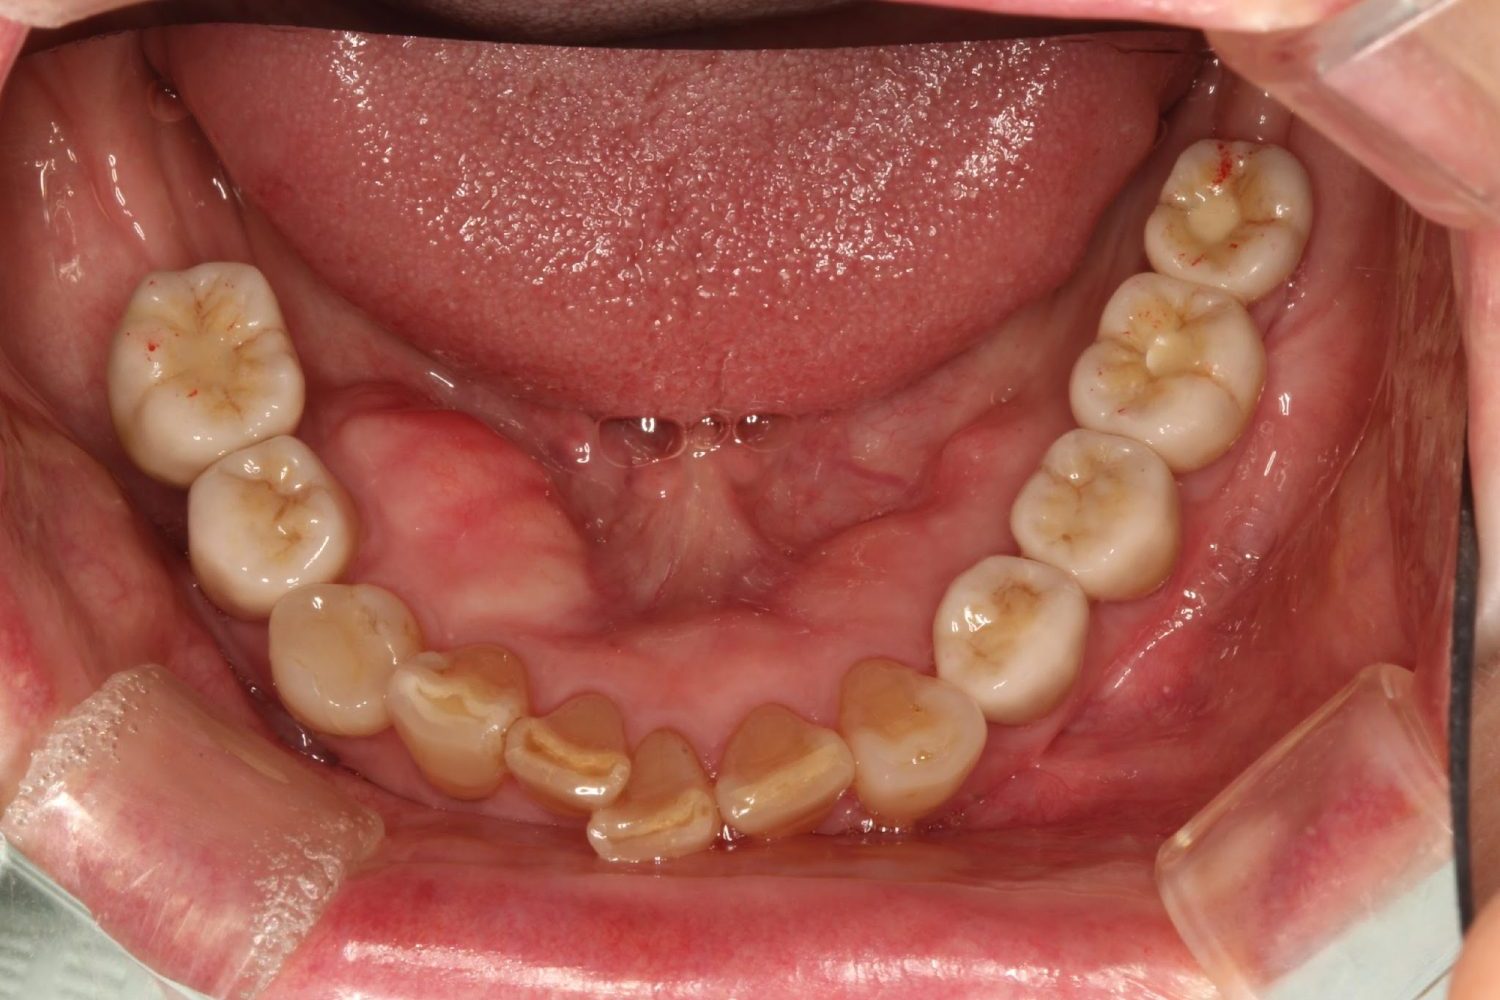

インプラント治療の症例紹介③

Before

After

主訴

むし歯の治療

治療内容

保存不可能な歯の抜歯

下顎にインプラント埋入し咬合再構成

治療費

2,688,400円(税込)

治療期間

14か月

治療回数

21回

想定されたリスク

※上部構造の形態が複雑になるため清掃が難しくなる。インプラント周囲炎の恐れがありました。

濱 仁隆先生

浜歯科

多数歯う蝕および多数歯欠損による咬合崩壊、保存不可能な歯の抜歯により上下無歯顎に。下顎に6本インプラント埋入する事で咬合再構成を行った。